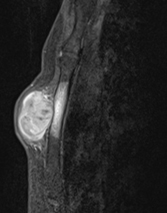

軟部腫瘍(悪性)